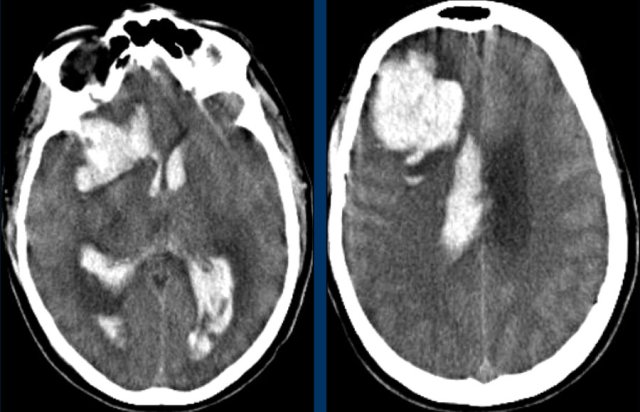

The first three images show a large hematoma in the basal ganglia on the right with massive edema.

The follow up image one year later shows  linear cavitation due to tissue loss (arrow) and hypodensity of the basal ganglia as a result of  gliosis.

This patient presented with hydrocephalus due to an intraventricular hemorrhage (left image).

Note the very small hyperdensity in the left thalamus, which is the origin of the hemorrhage.

Follow-up one day later (right image).

The patient  underwent surgery with placement of a ventricle drain to treat the hydrocephalus.

Note the hypodense thalamus on the left side with the persistent medially located hyperdense focus.